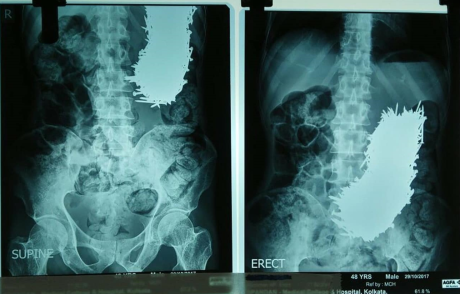

Jedan od zanimljivih slučajeva slučajnog gutanja jeste i veridba koja je krenula pogrešnim tokom. Naime, muškarac je stavio verenički prsten u milkšejk. Njegovo očekivanje je bilo da će devojka popiti piće i naći prsten na dnu. Ona je, međutim, progutala prsten u gutljaju. Situacija je bila i komična, jer nije htela da poveruje, budući da nije osetila ništa. Nakon svađe je pristala da uradi rendgenski pregled. Prsten je izbačen prirodnim putem. Veridba je ponovljena nakon detaljnog čišćenja, a venčali su se tri meseca kasnije.

Gutanje predmeta 3 Foto: www.huffpost.com

- Većina slučajeva gutanja predmeta, skoro 80 odsto, ne zahteva nikakvo medicinsko lečenje, a u preostalih 20 odsto su potrebne medicinske procedure. One mogu biti radiološke ili endoskopske. Prva radiološka procedura koja se radi je grafija grudnog koša i abdomena. Metalna strana tela (sem aluminijuma) i kosti se tako mogu videti. Plastika i riblje kosti se ne vide. Ukoliko se radi o oštrom predmetu ili postoji opasnost da je predmet otišao u disajne puteve, rade se i druge procedure. U manje od 1 odsto slučajeva je neophodna hirurška intervencija - objasnio je za eKlinika portal dr Aleksandar Ivković, specijalista radiologije.